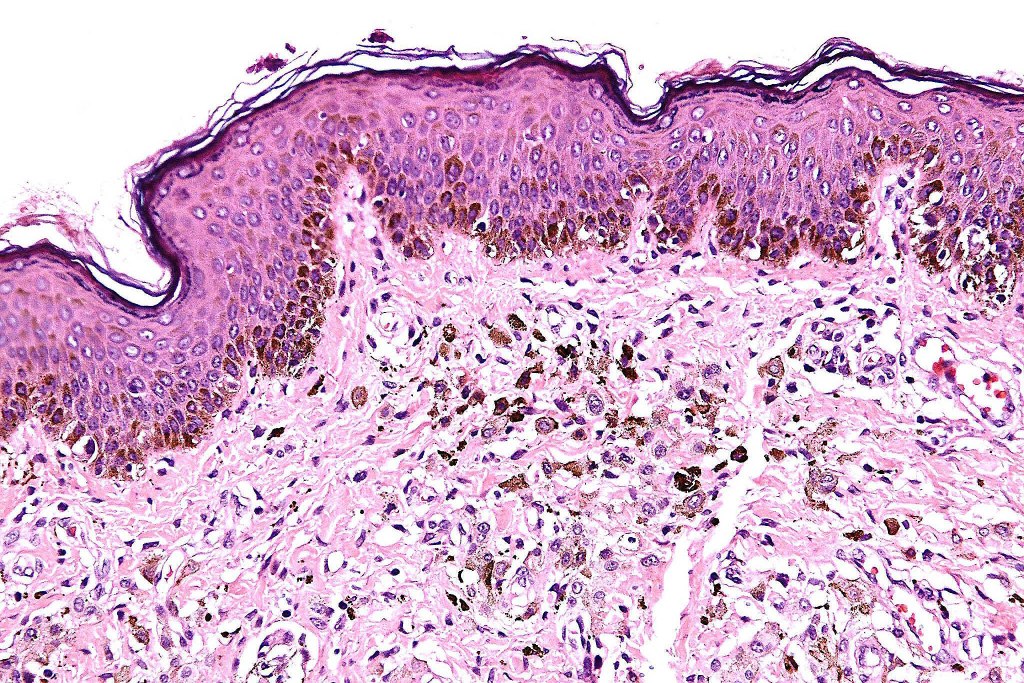

•Absence of necrosis, hemorrhage or Pagetoid spread in the overlying epidermis

•Spindle cell, small blue cell, blue nevus-like features, Spitzoid & proliferative nodules with mesenchymal differentiation (myofibroblastic, chondroid & osteoid) can be seen